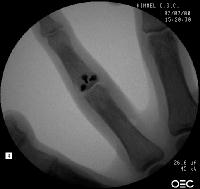

In the operating room, the crushed bone is removed and provisional fixation of the volar graft is obtained with Kirschner wires.

These wires are then replace, one at a time with micro screws.